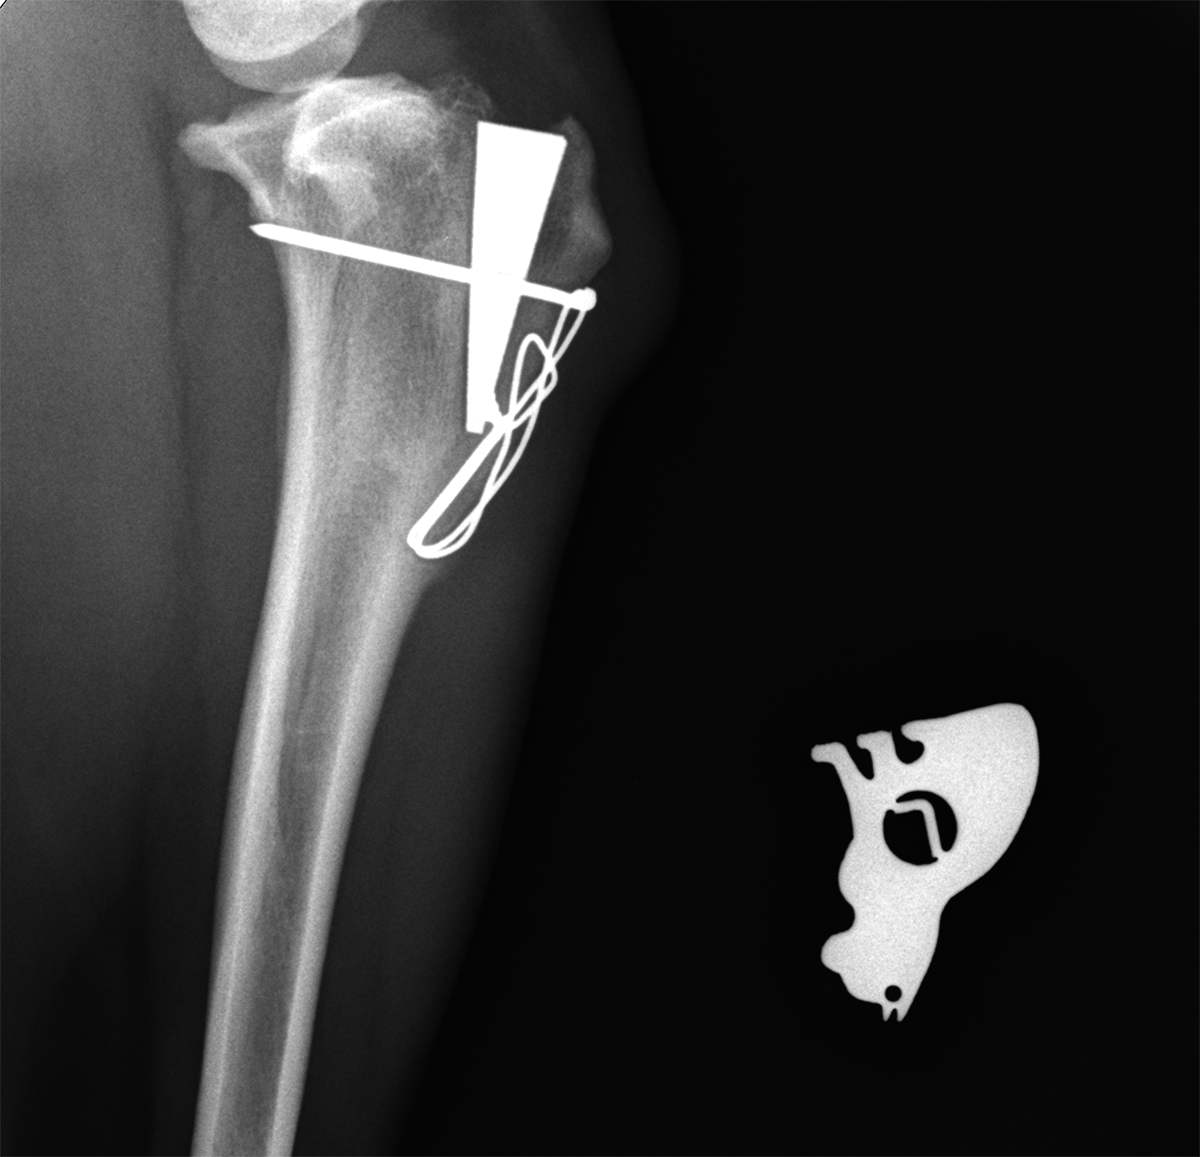

Renderización 3D de una tomografía computerizada posterior a una TTA. El avance tuberosidad tibial se consiguió mediante el implante de una cuña de titanio MMP. El cambio de fuerzas que consigue esta cirugía permite caminar al animal con normalidad, y en definitiva retrasar la evolución de la artrosis. La tomografía 3D y radiografía permiten ver la evolución de la cirugía con facilidad

Imagen radiográfica posoperatoria de una TTA MMP. Se aprecia claramente como el tejido óseo ya envuelve el implante. Por lo tanto se puede dar el alta al animal.